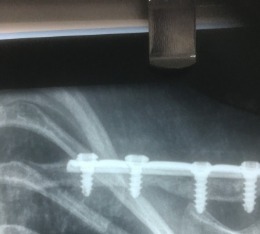

Συγγενής ψευδάρθρωση δεξιάς κλείδας

Κοριτσάκι έξι ετών με συγγενή ψευδάρθρωση δεξιάς κλείδας. Εξαιρετικό λειτουργικό αποτέλεσμα μετά από χειρουργική θεραπεία.